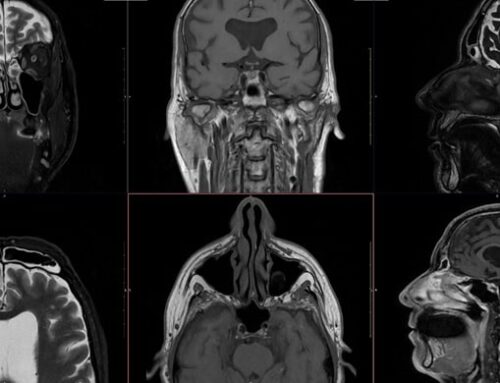

A ressonância é essencial para determinar o tamanho do tumor, sua relação com tecidos adjacentes e se houve disseminação para outros locais. Essa precisão é crucial na definição do plano terapêutico e na escolha entre cirurgia, quimioterapia ou radioterapia.

Durante e após o tratamento, a RM ajuda a avaliar se o tumor está regredindo e a identificar precocemente possíveis recidivas. Por ser um exame que pode ser repetido sempre que necessário, é ideal para o acompanhamento prolongado dos pacientes.

O exame é frequentemente solicitado em casos de câncer de cérebro, mama, fígado, pâncreas, próstata, colo do útero e reto, além de tumores ósseos e demais estruturas da face e pescoço. Em muitos desses casos, a ressonância oferece informações mais detalhadas do que outros exames de imagem.